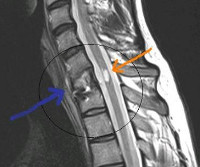

Яркая клиническая картина и тщательное неврологическое исследование позволяют неврологу диагностировать поражение спинного мозга и определить уровень локализации патологических изменений. Однако точно установить характер патологического процесса в спинном мозге на основании клинических данных не представляется возможным. Вспомогающее значение в диагностике гематомиелии имеет люмбальная пункция. Наличие крови в цереброспинальной жидкости свидетельствует в пользу кровотечения, но не всегда наблюдается при гематомиелии. Кроме того, следует учитывать, что кровь может попасть в спинномозговую жидкость из поврежденного в ходе люмбальной пункции сосуда.

Наиболее достоверными способами диагностики гематомиелии на сегодняшний день являются методы нейровизуализации: КТ и МРТ позвоночника. Для выявления артериовенозных мальформаций может применяться ангиография сосудов спинного мозга.